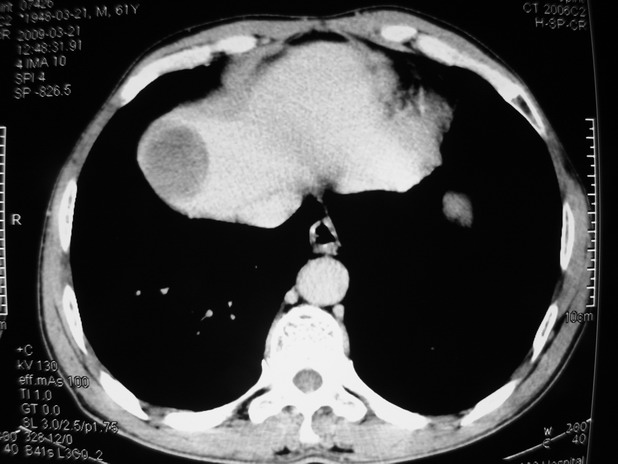

以下是引用余辉在2009-3-21 21:36:00的发言:[br]图像太乱了,建议楼主直接将强化数据按顺序列出来,病灶位置较表浅薄,有肝炎病史,灶内实性成分有显著强化,动脉期约60hu,考虑肝癌可能性大,进一步检查。